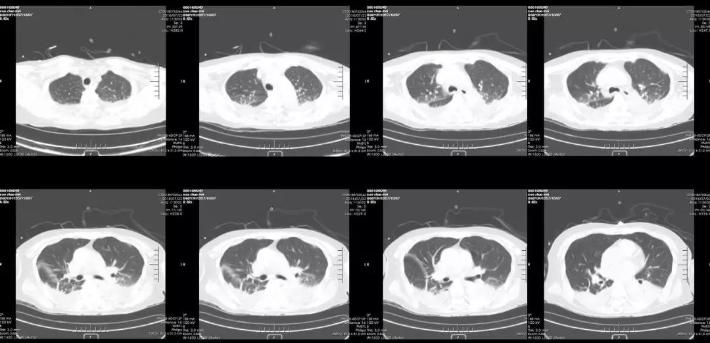

复查胸部CT

经上述处理后,患者病情趋于平稳,生命体征平稳,神志较前转清,自主呼吸好,血氧饱和度维持在98%以上。肺部感染好转。全身情况改善。